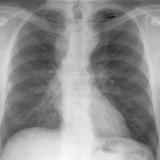

ASD 3 PA

Date: 03/17/2004

Views: 2337